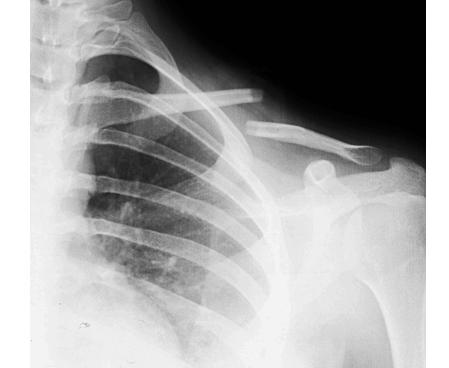

老李管不了电动车,赶紧打的就进来了医院急诊检查,结果片子一排,发现左边的锁骨从中间摔断了,而且骨头还错位了。老李左边锁骨中间鼓起来的那个“包”,其实并不是长了什么东西,而是断裂的骨折错位了,断开的骨头茬子从里面向外把皮给顶起来了。

锁骨骨折在生活中其实还是比较常见的,一般都是摔倒肩膀着地引起的,而且多见于儿童和年轻人。而且,锁骨骨折有个特点,那就是骨折最容易发生在中段,就像文章开头老李那样。

而锁骨中段骨折又有它自己特殊的地方。因为锁骨的上面有颈部肌肉向上牵拉,锁骨下面有胸部肌肉向下牵拉,所以一旦锁骨中段发生骨折,颈部的肌肉向上拉骨折块,胸部的肌肉向下拉骨折块,就会出现像下图一样典型的骨折移位。